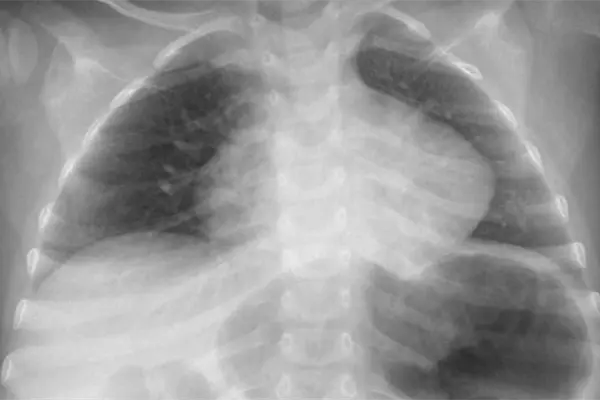

El pequeño Dylan, de apenas 2 años de edad, está delicado, ya que sufrió quemaduras graves en su esófago e infección en un pulmón, debido a que se tragó una pila, esto ocurrió en Hermosillo, Sonora.

La pila reventó en el interior de su organismo y provocó quemaduras en su estómago e infección en un pulmón.

La madre de Dylan, explicó que en un principio que lo llevó al Hospital de Cananea porque el niño presentaba dificultad para respirar y ahí le notificaron que había ingerido una pila.

Posteriormente, fue trasladado al HIES donde a través de diferentes aparatos oxigenan su sangre para poder operarlo.